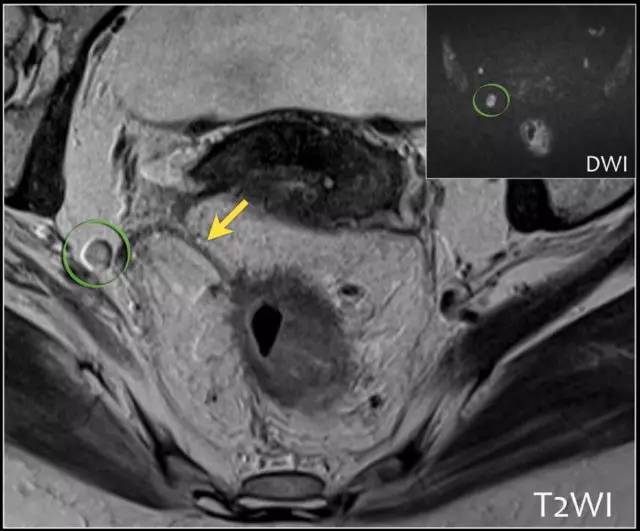

精确的淋巴结分期是重要的,因为转移淋巴结的数量影响预后。在 MRI 图像上确定淋巴结受累,传统上依赖于尺寸评估。然而反应性和转移性淋巴结之间,在尺寸上存在相当大的重叠。此外,正常大小的淋巴结中常见微转移。因此不提倡用大小来评估淋巴结是否存在肿瘤。

基于形状、边界和信号强度的标准已经被证明是更可靠的。使用这些标准,与组织病理学评估相比,MRI 确定淋巴结受累的准确度为 85%。然而阴性 MRI 成像不能排除淋巴结转移,因为成像技术不能确定淋巴结内的微转移。

以下是淋巴结分期诊断线索:

1. 均匀的淋巴结小于 10 mm,具有均匀信号强度不可疑。

2. 具有不规则边界和/或混合信号强度是可疑的。

3. 存在 1~3 个可疑淋巴结是 N1,存在 4 个或更多个是 N2。

4. 必须报告位于 CRM 1 mm 以内的任何淋巴结,因为它高度可疑 CRM 阳性。

5. 记录任何可疑骨盆侧壁淋巴结的位置和大小,这将改变放射治疗靶区。其次,外科医生将需要进行扩大淋巴结切除术(髂内淋巴结清扫)。

图 25 DWI 有助于检测淋巴结